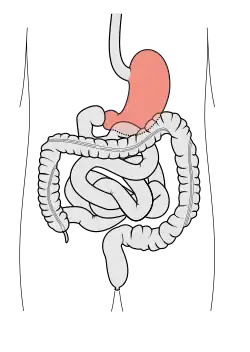

Aparato digestivo

El aparato digestivo está formado por el tubo digestivo y un conjunto de estructuras accesorias. El tubo digestivo se inicia en la boca y continúa por faringe, esófago, estómago, intestino delgado, intestino grueso y ano. Las estructuras accesorias son un conjunto de glándulas que vierten su secreción al tubo digestivo, incluyen las glándulas salivales que producen la saliva, páncreas, hígado y sistema biliar que transporta la bilis hasta el duodeno.

Los alimentos pasan de la boca al esófago hasta llegar al estómago. En el estómago el alimento se mezcla con una secreción ácida y enzimas proteolíticas hasta formar una pasta semilíquida que recibe el nombre de quimo.[25] El contenido del estómago se vacía en el duodeno, donde se añade la bilis producida por el hígado y el jugo pancreático del páncreas.[26][27] En el intestino delgado es donde se absorben los nutrientes, después el intestino grueso absorbe sobre todo agua y sales minerales.[28] Finalmente, las sustancias restantes pasan al recto y se excretan por el ano.[29]